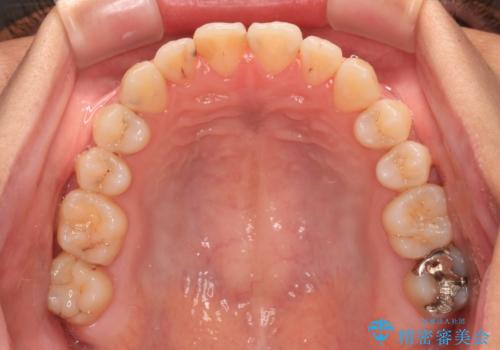

前歯のクロスバイトを治したい ワイヤー装置による矯正治療

- 前歯の反対咬合を気にして来院された患者様です。

マウスピース矯正も提案しましたが、しっかりと使用する自信がないとのことで、ワイヤー装置により矯正治療を行うこととしました。

クロスバイト改善まではスムーズに進みましたが、その後は強い舌の突出癖によりオープンバイトの期間が長く続きました。

舌のトレーニングをしっかりと実施してもらい、何とか仕上げることができました。